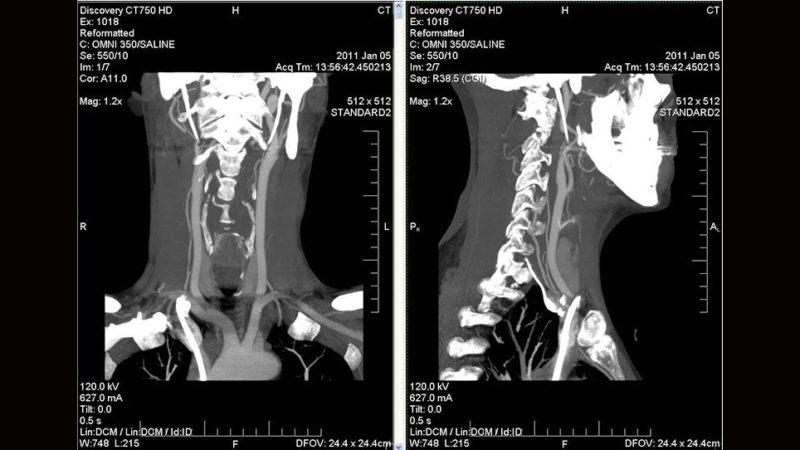

Как выглядит снимок КТ, можно увидеть на фото КТ шейного отдела позвоночника.

КТ шейного отдела проводится для диагностики шейных позвонков, гортани, глотки, шейных мышц и связок, щитовидной и других желез, сосудов. Что показывает КТ шейного отдела позвоночника? Она позволяет определить травмирование шейных позвонков, подозрение на онкологию, воспаление глотки или гортани, изменения в костной ткани, деформацию или смещение позвонков.